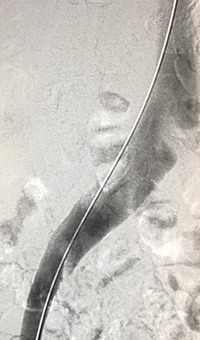

xray image of Iliac vein post-ZelanteDVT.

Iliac vein post-ZelanteDVT

xray image of liac vein post-PTA & stent.

Iliac vein post-PTA & stent